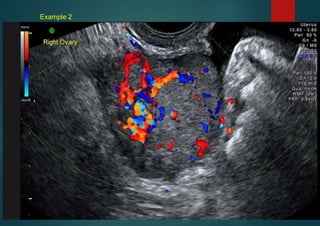

Example 2

Simple rules:MALIGNANT

Metastasis from bowel primary